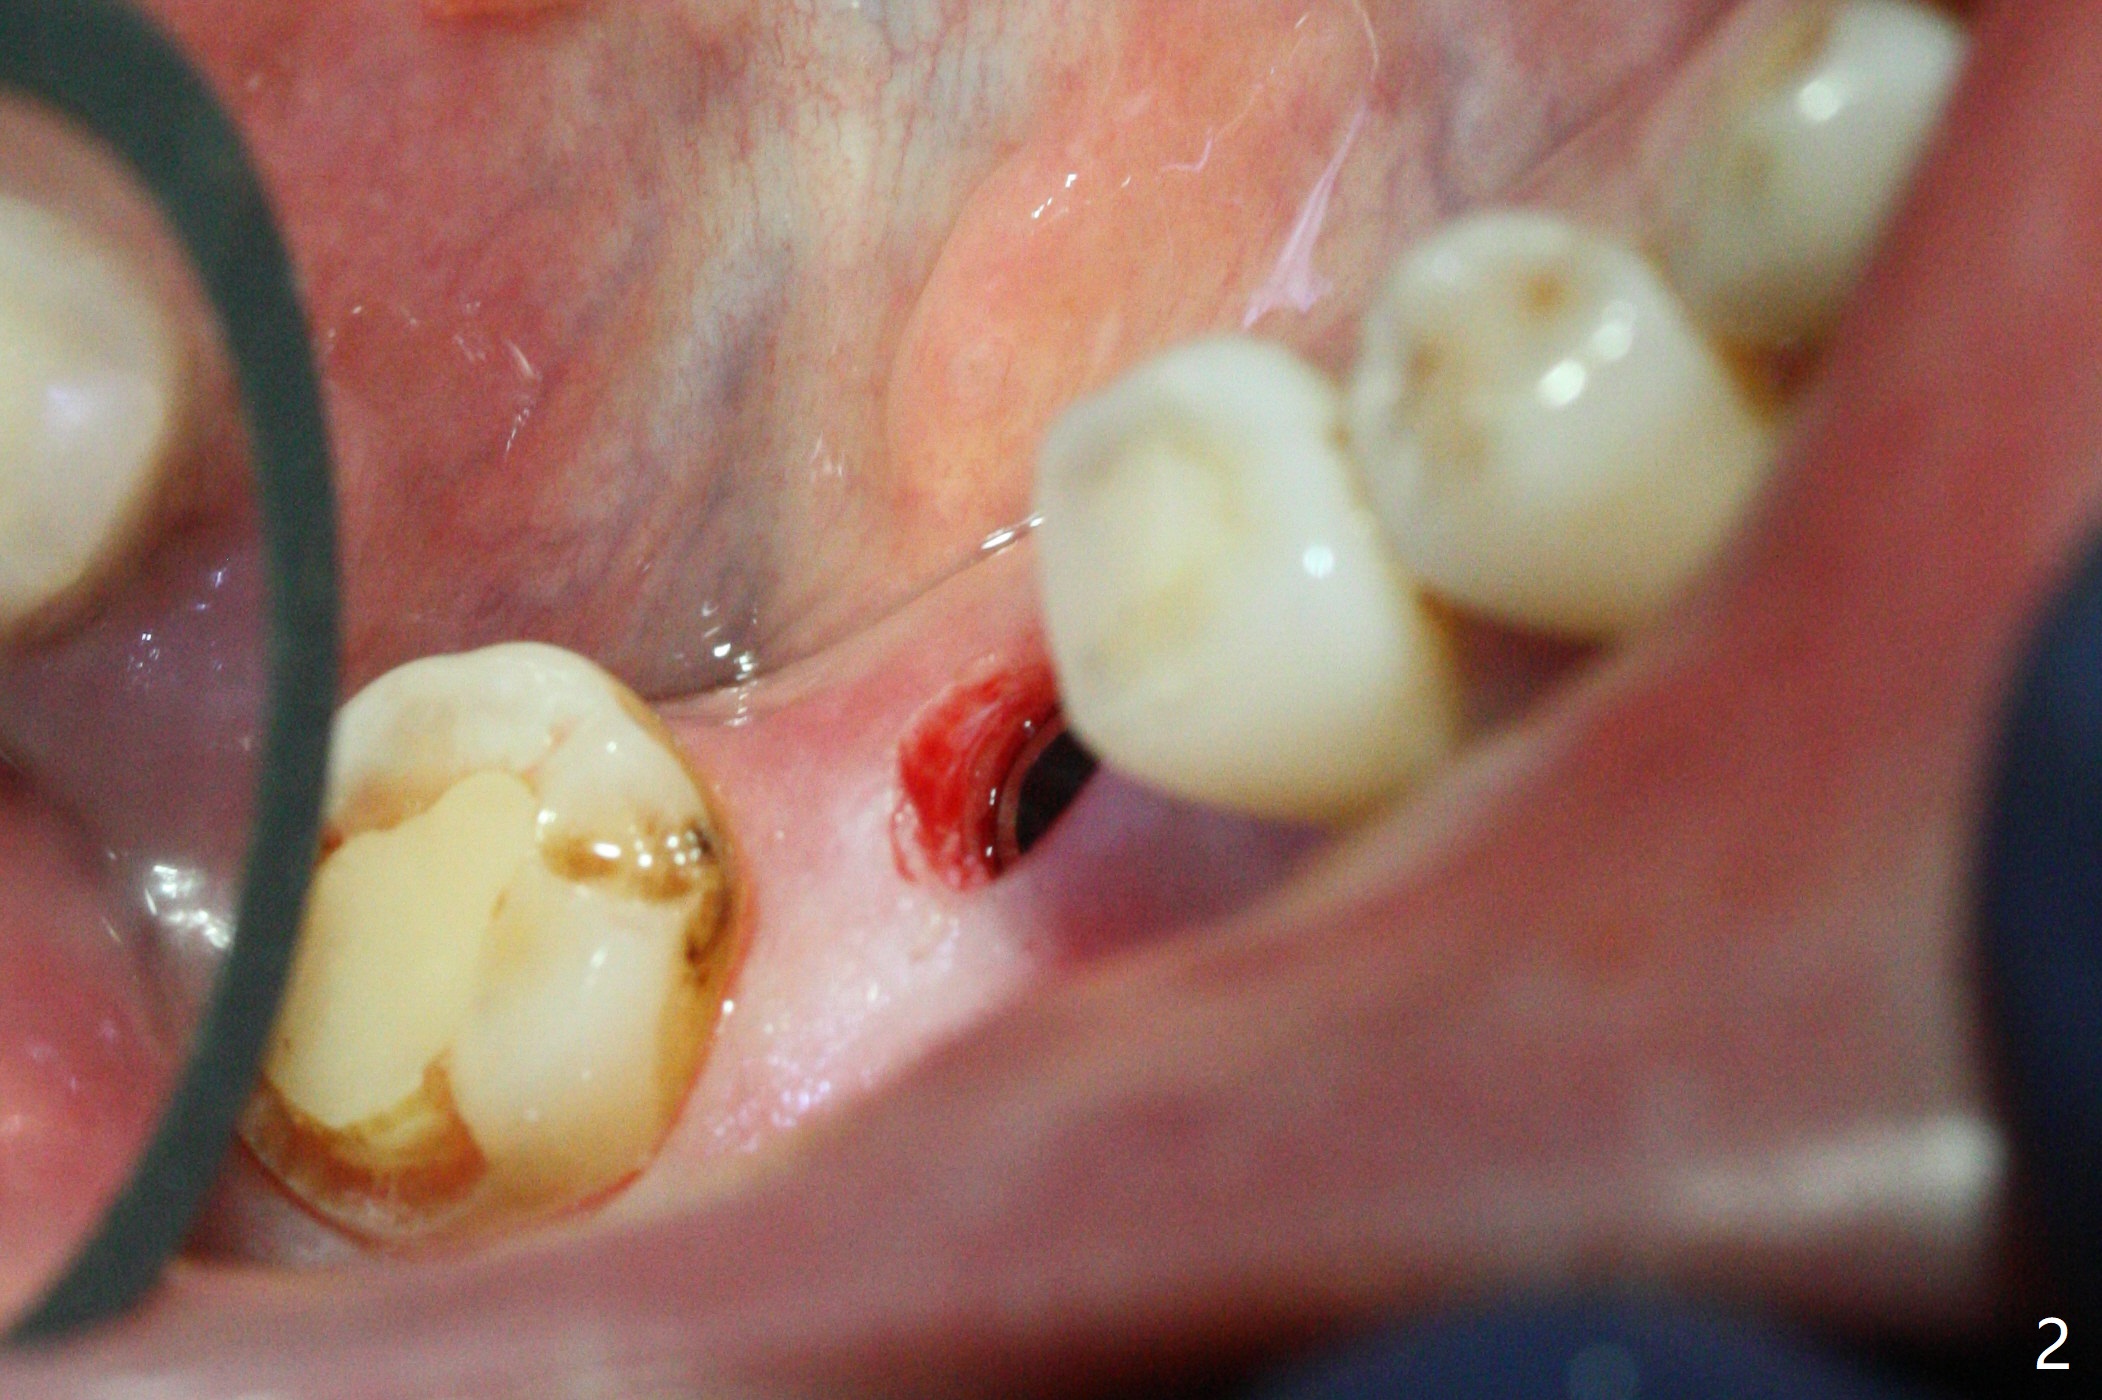

A 5x10 mm implant is placed at #30 with a surgical guide (Fig.1 *) in 10 minutes. The most amazing part of this surgery is that the guide allows you to place the implant at the precise level care-free (~ 1 mm subcrestal, Fig.2,3). Everything happens so quick that when a 5.5x3 mm healing abutment is placed (Fig.4), you are pleased to feel that the implant is stable (Fig.5). You could not ask for anymore. The fearful patient reports no postop pain. The implant is placed as planned (Fig.6, overlap image provided by the guide designer, Jennifer). The patient returns for impression nearly 2 months postop (Fig.7,8). It appears that the implant has osteointegrated without bone loss (Fig.7). The soft tissue is healthy around the just placed cementation abutment (Fig.8 (5.2x4(2) mm)). When the permanent crown is seated initially 2.5 months postop, the mesial contact is slightly tight and the occlusion is high. Bitewing shows the distal open margin (Fig.9 >). After mesial contact adjustment, the patient feels that the occlusion is better. With further occlusal adjustment, the crown is cemented without distal open margin (Fig.10). The patient returns to her home country for 3 months. The implant is doing well 3.5 months post cementation; impression is taken for #14 surgical guide.